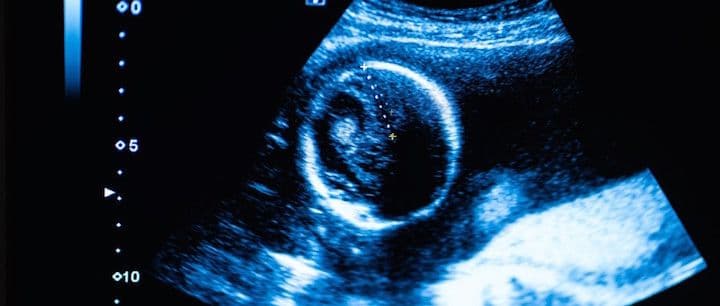

The first part of the pregnancy that can be seen is the gestational sac. The gestational sac can be seen around cycle days 32-35, which is about 18-21 days after ovulation/fertilization. However, sometimes it can take a couple of days longer to see the gestational sac on transvaginal ultrasound. On abdominal ultrasound, the sac can be seen several days later.

The gestational sac is a structure that surrounds the embryo and can be seen even before the embryo is visible. About 7-10 days later, the embryo can be seen on transvaginal ultrasound (at approximately 6 weeks, 3 days). You can likely now also see the fetal heartbeat.